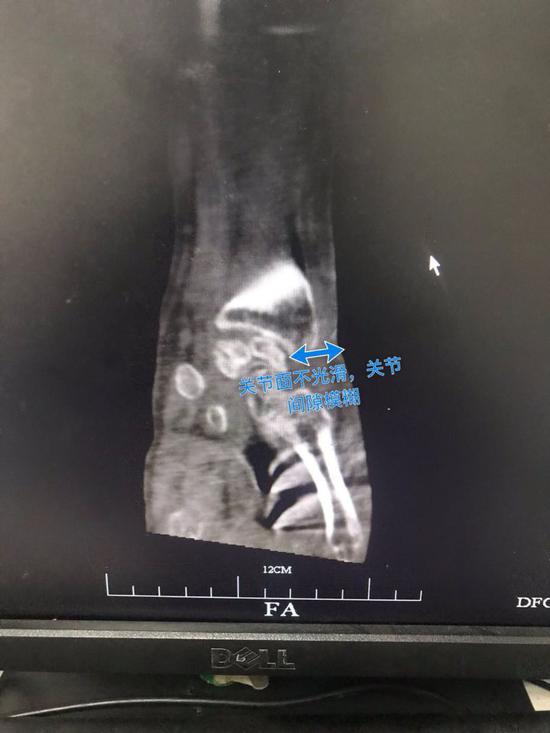

過了一個星期,姚先生才發現事情不對勁,他的右腕關節開始持續疼痛,小拇指還有大拇指變得腫脹,還有流膿的情況,他趕到余姚當地以及寧波的醫院就診,掛號的科室都是“類風濕關節病”,“我還以為是關節自己的問題?!币ο壬f,畢竟天天和海產品打交道,周圍人患有類風濕關節病的不在少數。

半年之后,姚先生找到了杭州的一家醫院,檢查顯示姚先生的右手腕持續流膿,伴隨著惡臭和疼痛,CT片顯示膿腫肌腱斷裂,醫生告訴姚先生,這種情況可能要截肢……